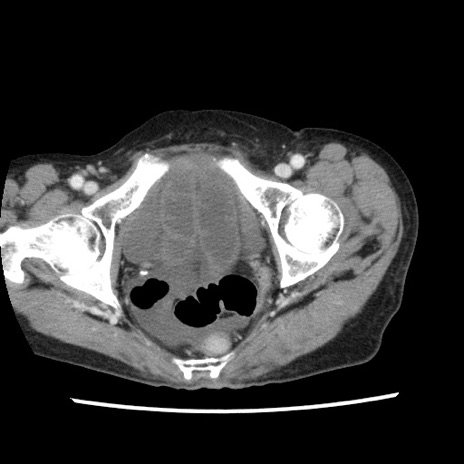

矢状断像

【症例】80歳代女性

【主訴】腹痛

【現病歴】8時間前から腹痛あり来院。

【既往歴】糖尿病、脂質異常症、子宮体癌にて子宮全摘術

【身体所見】意識清明・会話良好だが腹痛で苦悶様、全腹部にわたって反跳痛と圧痛あり

【データ】WBC 13600、CRP 0.14、LDH 224、CK 90